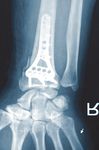

C1 Fraktur, Versorgung mit volarer Platte (breit) und Ulna-Hakenplatte

Präoperativ

Postoperativ

Klinischer Fall und CT-Aufnahmen mit freundlicher Unterstützung der

Klinik und Poliklinik für Unfall-, Hand- und Wiederherstellungschirurgie

Universitätsklinikum Gießen und Marburg GmbH